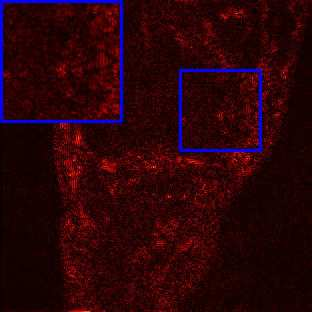

Limited by imaging systems, the reconstruction of Magnetic Resonance Imaging (MRI) images from partial measurement is essential to medical imaging research. Benefiting from the diverse and complementary information of multi-contrast MR images in different imaging modalities, multi-contrast Super-Resolution (SR) reconstruction is promising to yield SR images with higher quality. In the medical scenario, to fully visualize the lesion, radiologists are accustomed to zooming the MR images at arbitrary scales rather than using a fixed scale, as used by most MRI SR methods. In addition, existing multi-contrast MRI SR methods often require a fixed resolution for the reference image, which makes acquiring reference images difficult and imposes limitations on arbitrary scale SR tasks. To address these issues, we proposed an implicit neural representations based dual-arbitrary multi-contrast MRI super-resolution method, called Dual-ArbNet. First, we decouple the resolution of the target and reference images by a feature encoder, enabling the network to input target and reference images at arbitrary scales. Then, an implicit fusion decoder fuses the multi-contrast features and uses an Implicit Decoding Function~(IDF) to obtain the final MRI SR results. Furthermore, we introduce a curriculum learning strategy to train our network, which improves the generalization and performance of our Dual-ArbNet. Extensive experiments in two public MRI datasets demonstrate that our method outperforms state-of-the-art approaches under different scale factors and has great potential in clinical practice.